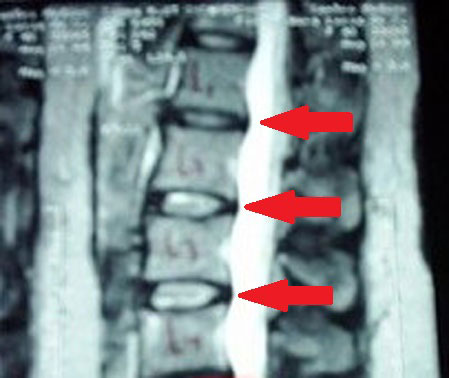

Persistindo a degeneração do disco, sem tratamento, ocorre a protrusão do núcleo pulposo, que é o centro do disco:

Protrusões dos discos entre as vértebras Lombares 1 e 2; 2 e 3; 3 e 4, marcados pelas setas. Em branco, o saco dural, preenchido de líquor (onde estão os nervos finais da medula espinhal, "embebidos" em um líquido chamado líquor). Neste estágio, já começa a haver certa compressão com alguns sintomas.